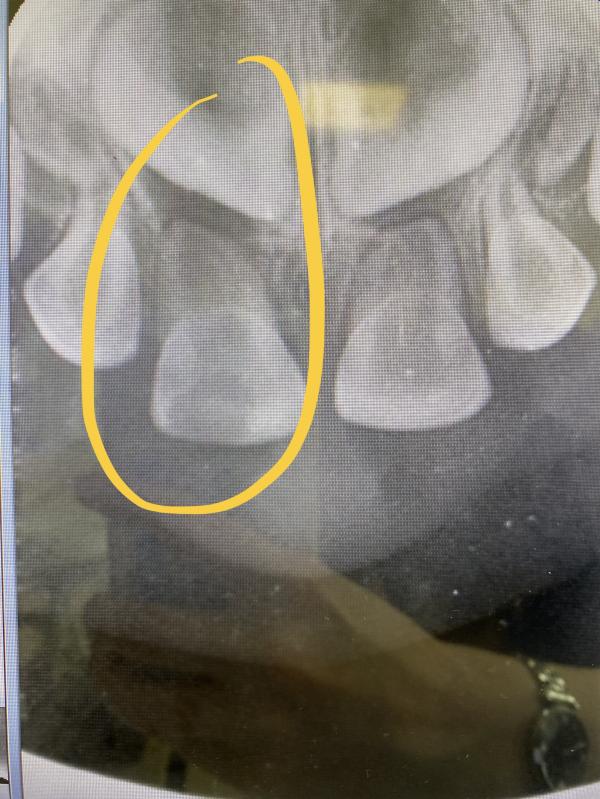

В прошлом году ударилась зубом - скол. В стоматологии сказали не трогать. Подрастет - подпилить можно будет.

Но сейчас ребёнок жалуется на зубную боль.

Поехали снова в стоматологию, предложили удалить или понаблюдать несколько дней спадет ли боль, не будет ли отека губы. Выбрали второй вариант.